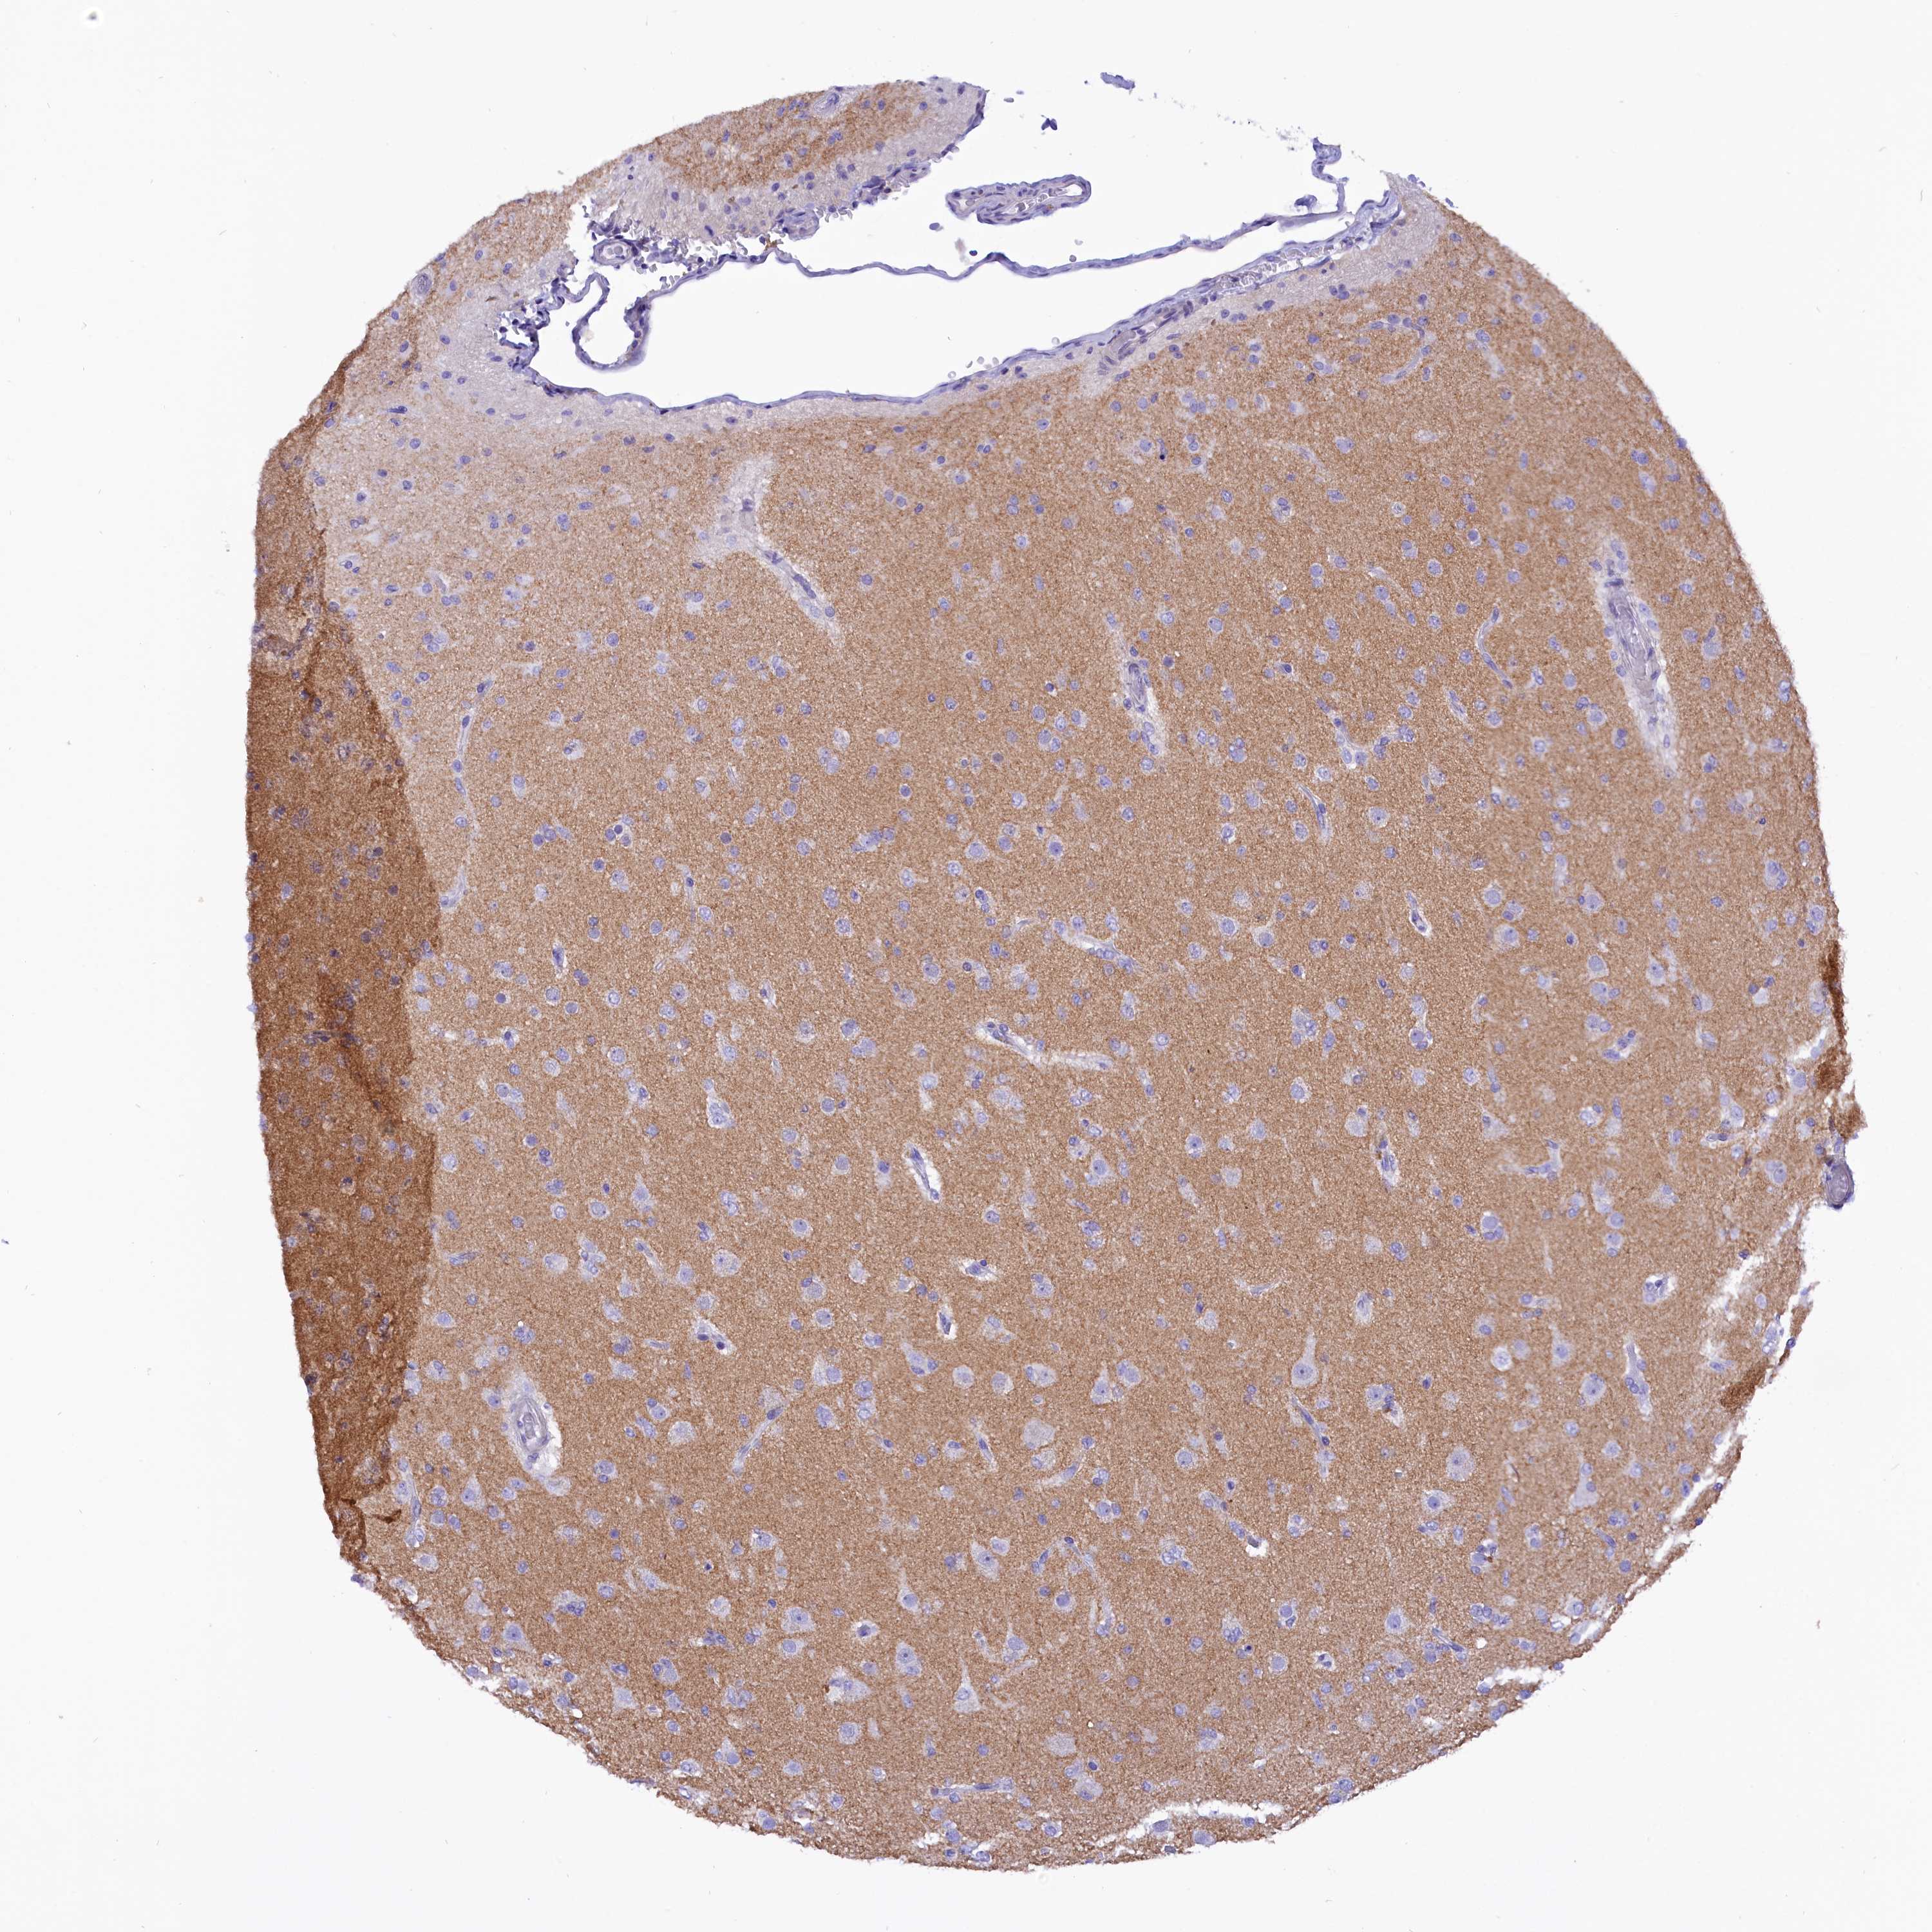

GLIOMA - Protein expressioni

A mouse-over function shows sample information and annotation data. Click on an image to view it in a full screen mode. Samples can be filtered based on level of antibody staining by selecting one or several of the following categories: high, medium, low and not detected. The assay and annotation is described here.

Antibody stainingi

Antibody staining in the annotated cell types in the current human tissue is reported as not detected, low, medium, or high, based on conventional immunohistochemistry profiling in selected tissues. This score is based on the combination of the staining intensity and fraction of stained cells.

Each image is clickable and will lead to virtual microscopy that enables deeper exploration of all samples and also displays staining intensity scores, fraction scores and subcellular localization as well as patient and tissue information for each sample.

Antibody HPA043138

Staining

High

Medium

Low

Not detected

Intensity

Strong

Moderate

Weak

Negative

Quantity

>75%

75%-25%

<25%

None

Location

Nuclear

Cytoplasmic/membranous

Cytoplasmic/membranous,nuclear

Glioma, malignant, High grade

Glioma, malignant, Low grade